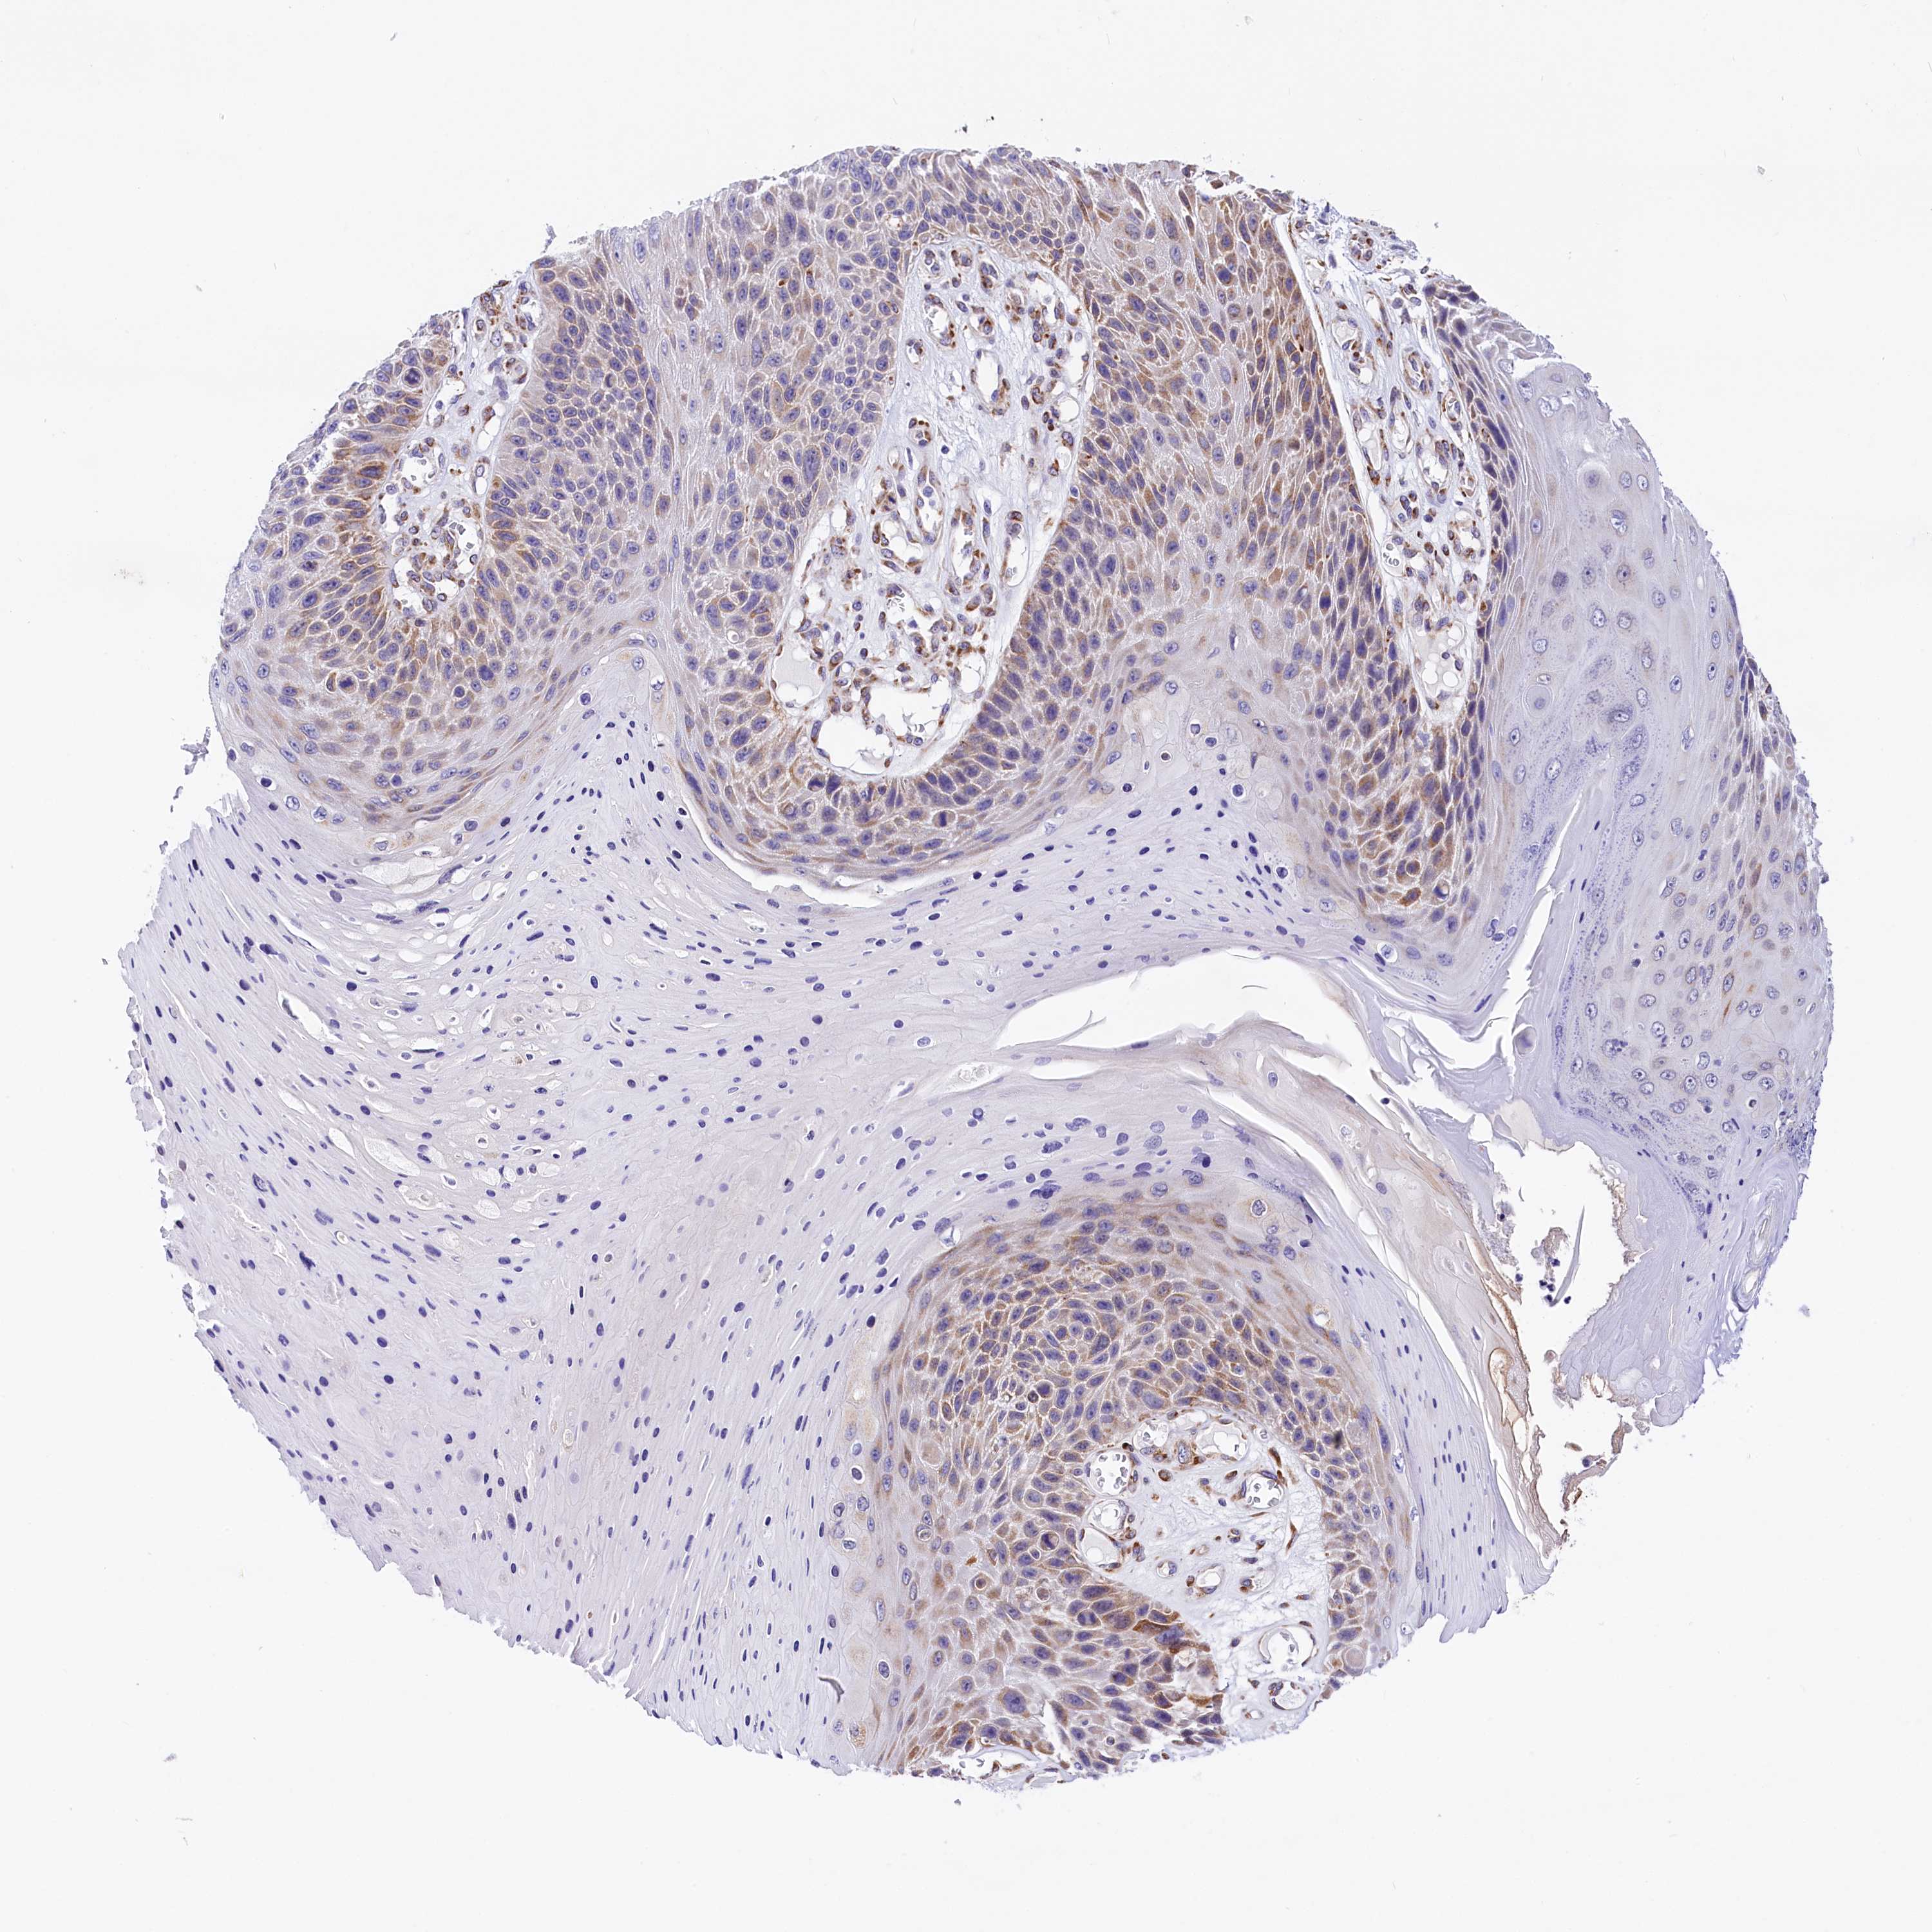

SKIN CANCER - Protein expressioni

A mouse-over function shows sample information and annotation data. Click on an image to view it in a full screen mode. Samples can be filtered based on level of antibody staining by selecting one or several of the following categories: high, medium, low and not detected. The assay and annotation is described here.

Antibody staining in the annotated cell types in the current human tissue is reported as not detected, low, medium, or high, based on conventional immunohistochemistry profiling in selected tissues. This score is based on the combination of the staining intensity and fraction of stained cells.

Each image is clickable and will lead to virtual microscopy that enables deeper exploration of all samples and also displays staining intensity scores, fraction scores and subcellular localization as well as patient and tissue information for each sample.

Antibody HPA042555

Staining

High

Medium

Low

Not detected

Intensity

Strong

Moderate

Weak

Negative

Quantity

>75%

75%-25%

<25%

None

Location

Nuclear

Cytoplasmic/membranous

Cytoplasmic/membranous,nuclear

Squamous cell carcinoma, NOS